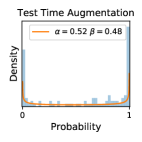

5.1 Distribution of Uncertainty Scores

Distribution of Uncertainty Scores Across Different Severity Levels As explained in Section 3, each uncertainty metric essentially defines an order/ranking among the data points. We conducted an analysis to better understand what data will be assigned high uncertainty under a particular uncertainty metric . Picking out the highest ranked data points (), we calculated the ratio of data points from each SL. Figure 4 summarizes the results as box plots for the Kaggle-DR and the Messidor-2 datasets; additional detailed statistics can be found in Table S.1 in the supplementary materials. From the plot and table, SL1 & SL2 examples account for a higher proportion among the top-ranked uncertain examples across the three ensemble methods. This finding matches our intuition that incipient disease examples (SL1 & SL2) are more likely to be considered uncertain by ensemble methods due to their ambiguity.

In contrast, the MC-dropout method showed the worst overall performance among the three, as it can be seen from the high ratios of SL0 examples among the uncertain negatives in Figure 4. The histograms in Figure 2 provides another perspective to look into the phenomenon, where a decent proportion of MC-dropout model’s predictions on SL0 inputs entailed low confidence (far from 0 or 1), which from another angle explained why MC-dropout was less specific in terms of lower FNP; many no-DR inputs (i.e. SL0) were erroneously assigned high uncertainty by MC-dropout models.

As discussed in Section 5.1 and Section 5.3 in the main paper, the mean metric and the stacking ensemble will have better performance in the precision (specificity) on the ambiguous data. Here, more detailed results are shown in Figures S.3 & S.6 and Table S.1. Figures S.3 & S.4 show the histograms of the uncertainty score for Kaggle-DR and Messidor-2 datasets that are the in-distribution (i.d.) dataset in our experiment and FigureS.5 & S.6 show the histograms for ImageNet and CIFAR-10 datasets, which is the o.o.d. datasets in our experiment. Each group of histograms contains results from the three evaluated ensemble methods (stacking ensemble, MC-dropout and TTA) and the three uncertainty metrics (mean, var and kl). Additional detailed results not displayed in Figure 4 can be found in Table S.1, which shows the proportion of the data of different SLs varies across different . For comparison, we also included in Table S.1 the results from single learners, and the proportions of data of different SLs (before any selection was made).